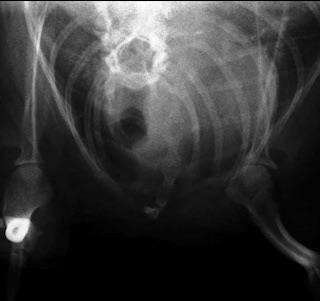

最近症例報告出来ていなかったので報告します。症例は3歳の若いチワワなのですがホームドクターで1歳の時にすでに気管虚脱と診断されています。初診時で頸部気管虚脱グレード3-4と診断しています。手術適応症例でした。またレントゲンでは後天的と思われる漏斗胸も確認出来ました。

レントゲンでは確認出来なかったのですがこの症例は術中に肺ヘルニアを確認しました。咳や胸腔内圧が高かった状態を推察しました。気管支鏡でも重度の狭窄を確認して手術しました。